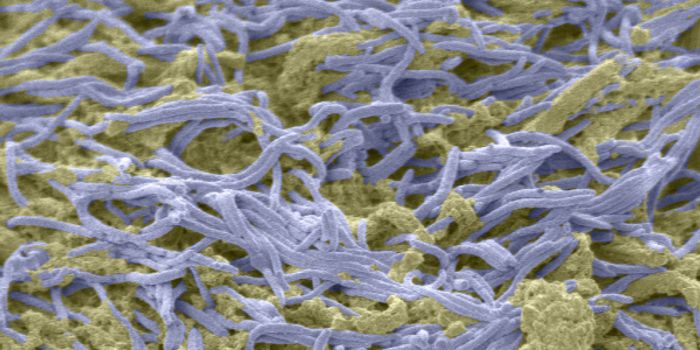

AUG 25, 2016MicrobiologyResearchers have learned more about how Lyme disease invades the body, and will publish their findings September 6 in Ce ...